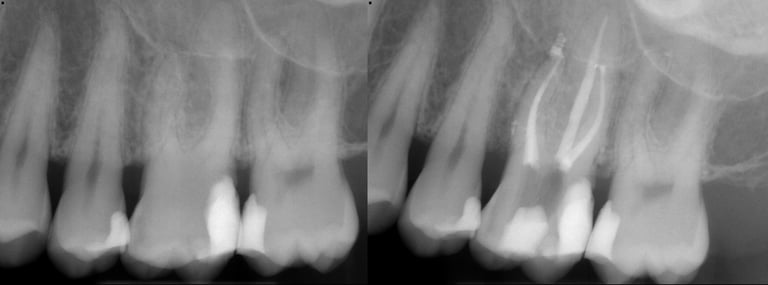

Gallery 1: Initial Cases

Initial Root Canal Cases with preoperative and postoperative radiographs.

#31 RCT

#5 RCT with 3 canals